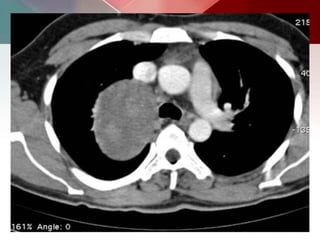

b) Hydatid cysts:

 Hydatid cysts may be solitary or multiple, the number

depending mainly on the amount of ova ingested and

the number of embryos filtered through the liver and

lungs.

 A centrally located cyst is said to be usually round,

but may become oval or polycyclic. Inferior lobes most

commonly affected

 Intact: ruptured= 3:1

Calcified unilocular hydatid cyst. Contrast material enhanced

CT scan shows a round lesion with water attenuation and a ring like pattern of

calcification (arrows). This pattern represents calcification of the peri-cyst and

strongly suggests a diagnosis of hydatid cyst